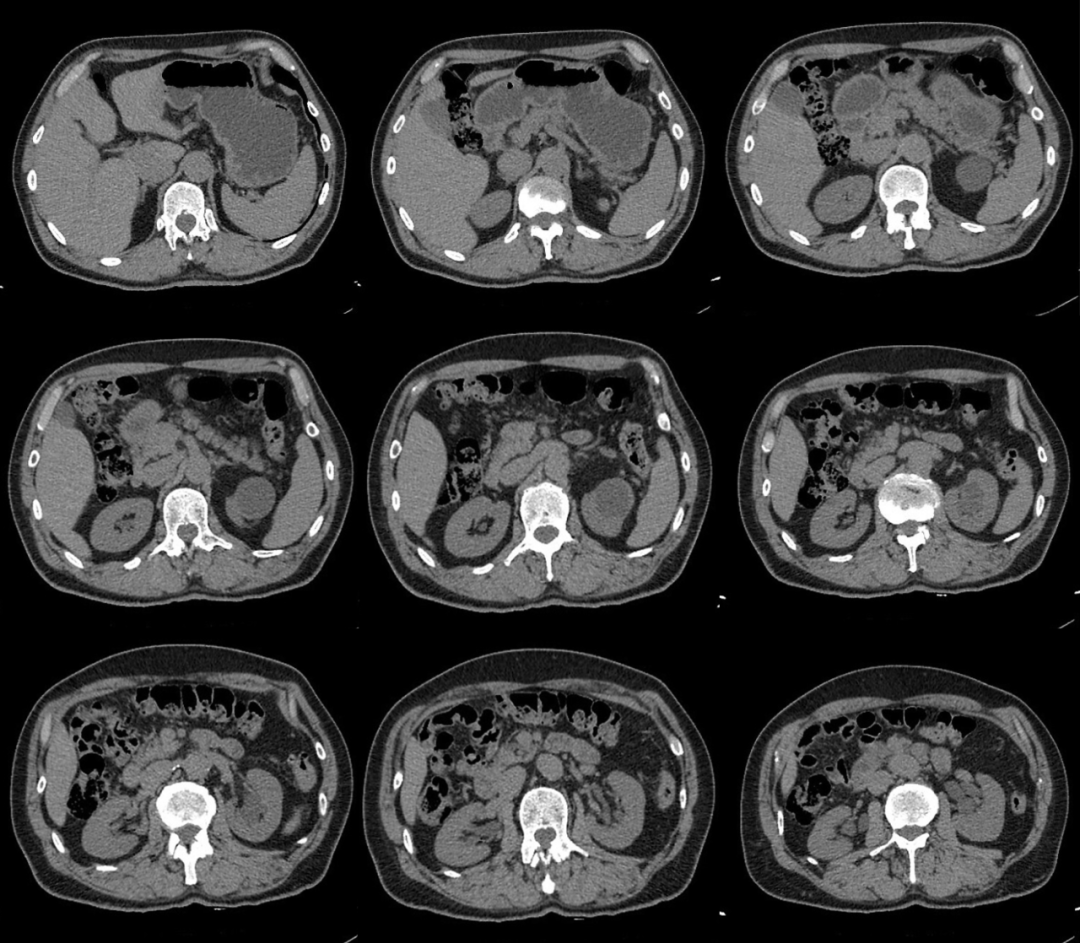

患者男性 43 岁 因左侧腰背部疼痛不适,左侧腰背部叩击疼阳性,门诊拟:「 肾结石 」 行 CT 检查;

咦!没有发现明显的阳性结石啊,就左肾囊肿;

嗯,真的就是囊肿嘛?

我们建议 CT 增强扫描;